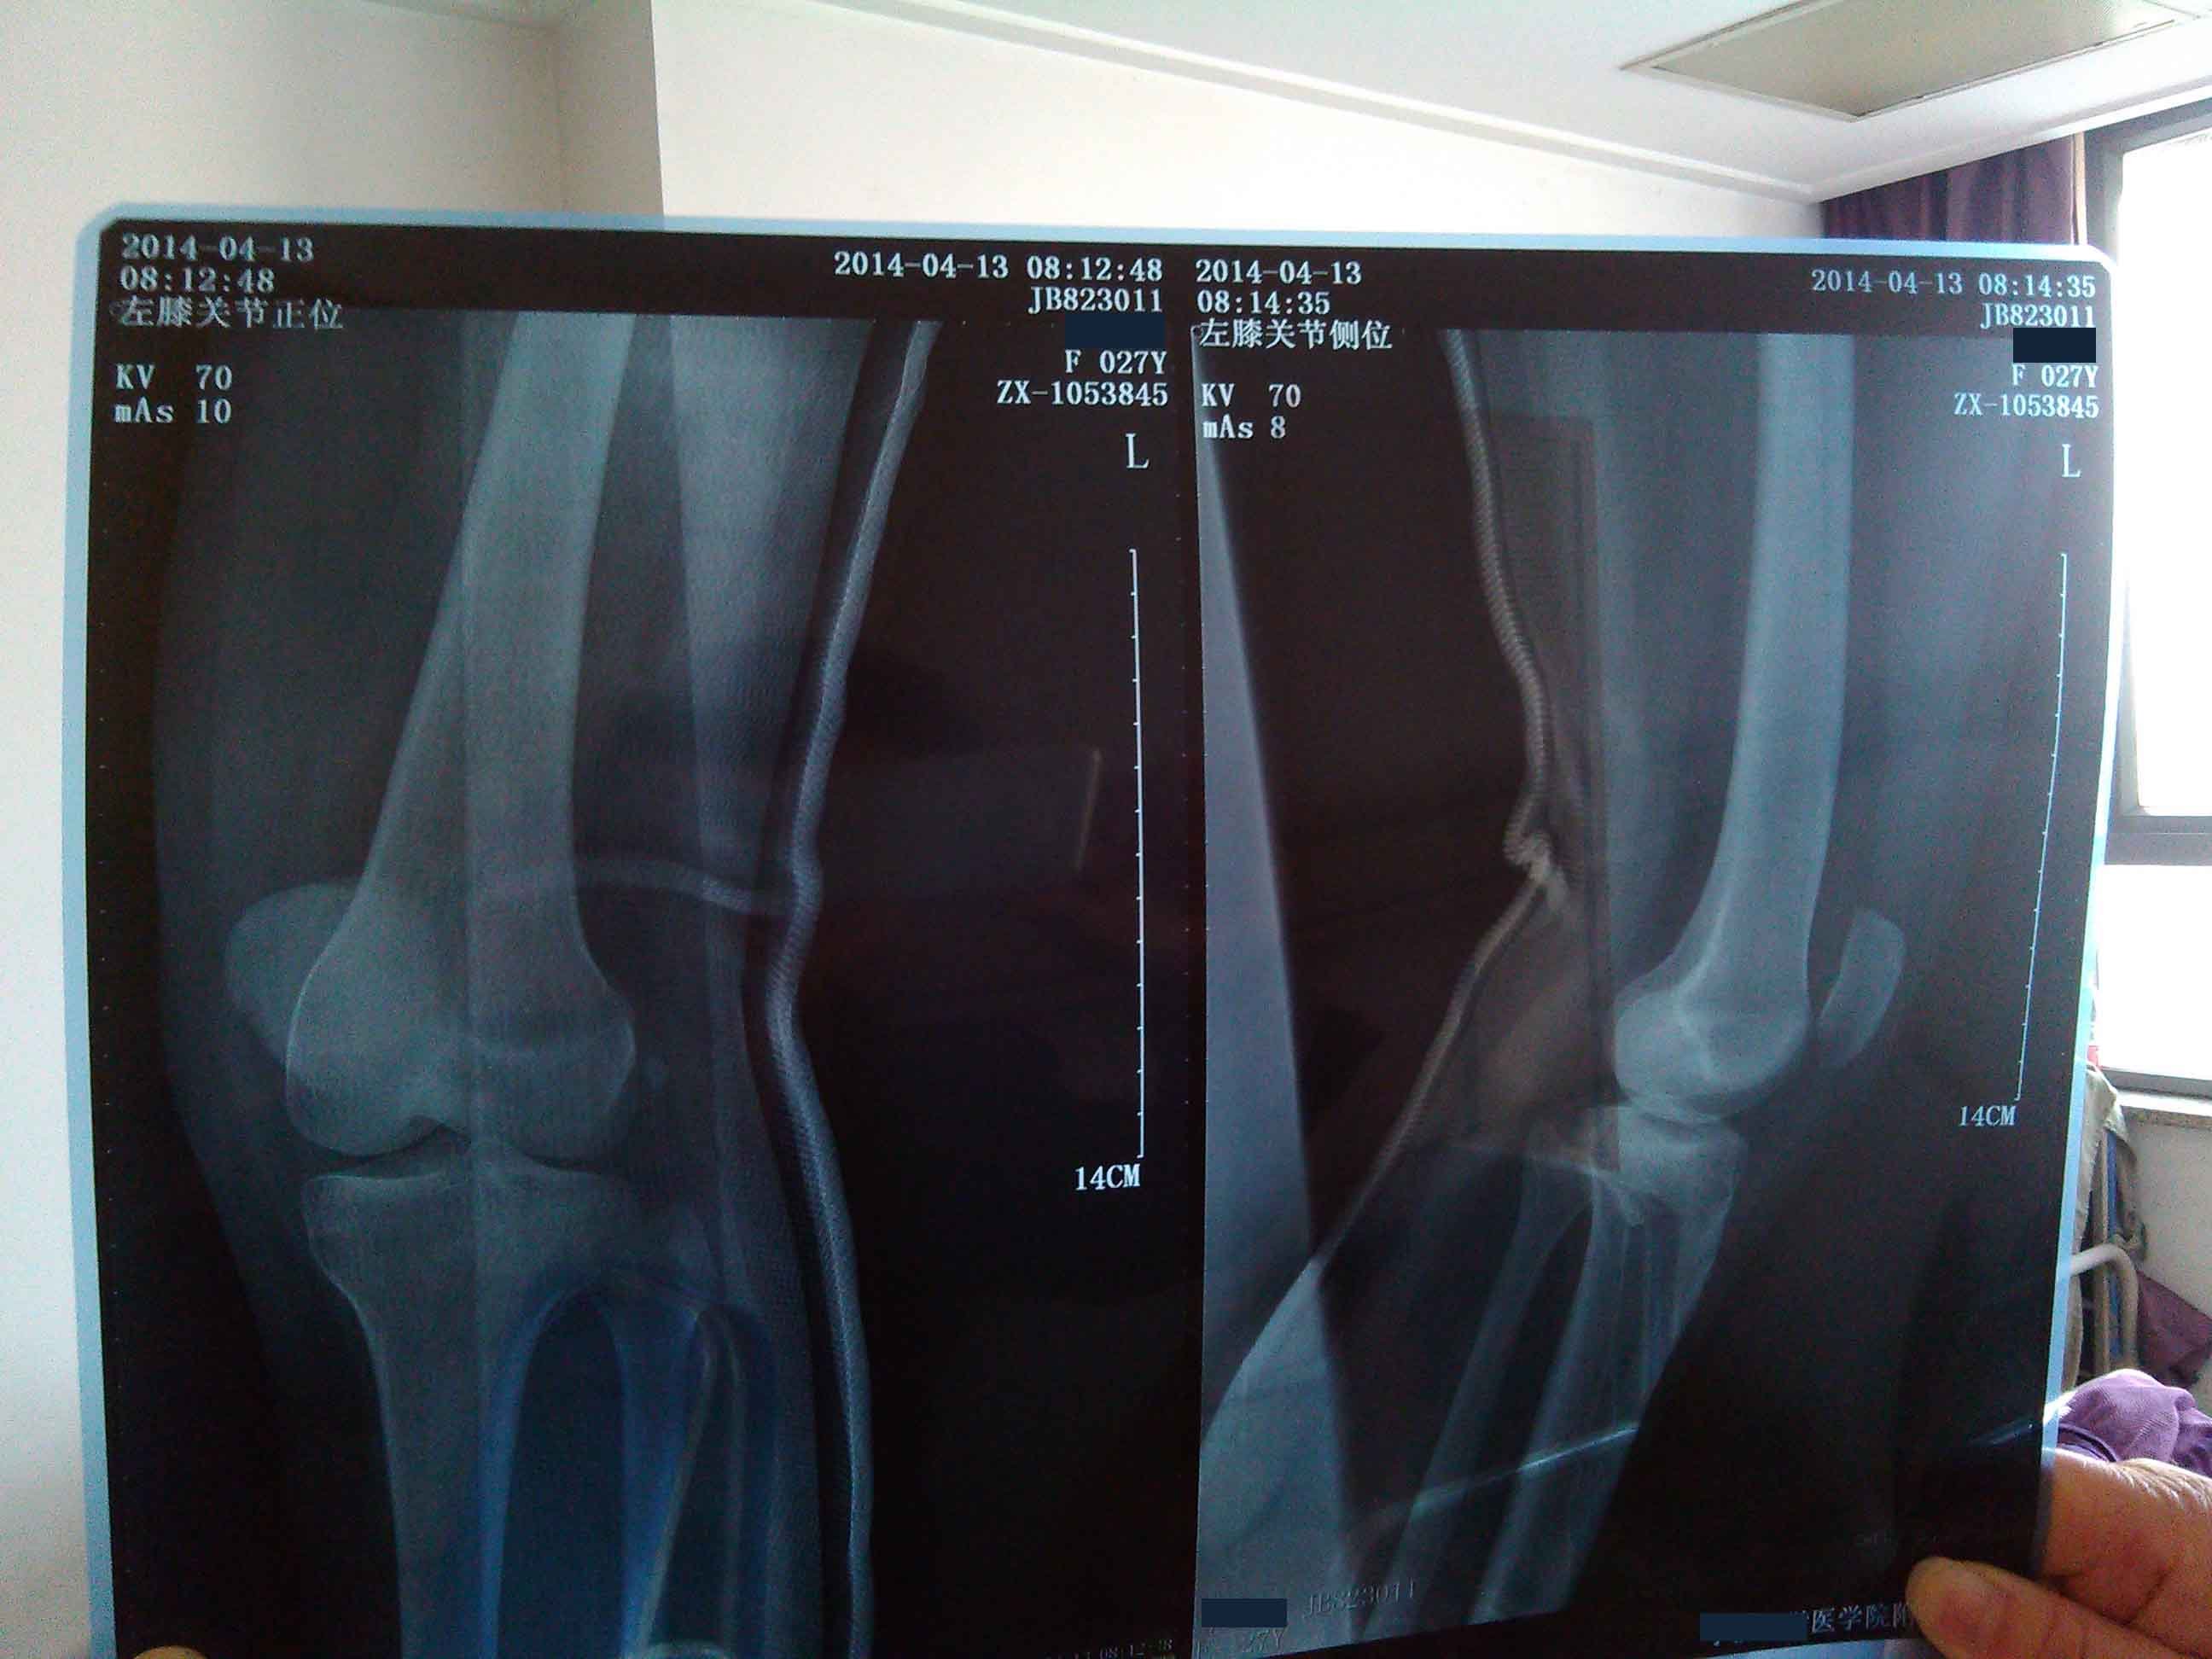

好医生?我是孕妇由于什么药也用不了 帮我看看这片子严重吗 医院医生说骨折处可以长好 现在打石膏第8

病情分析: 照的片子的清晰度不是太好,好像是腓骨有一些骨折。髌骨的位置也不正常。 指导意见: 骨折的部位是完全可以恢复正常的,如果韧带有断裂的情况,必须手术治疗才可以治愈。